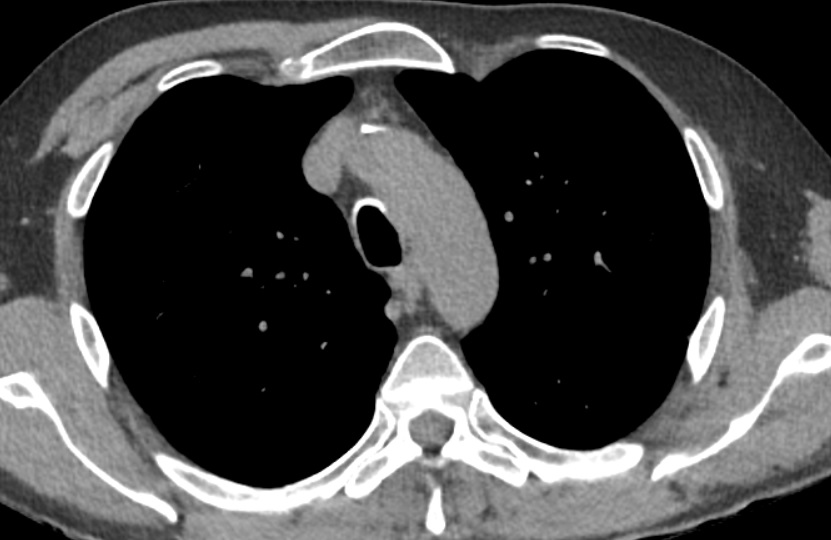

- Absence unilatérale de grand pectoral

- Crée une clarté artificielle sur les RX Thorax

Cas